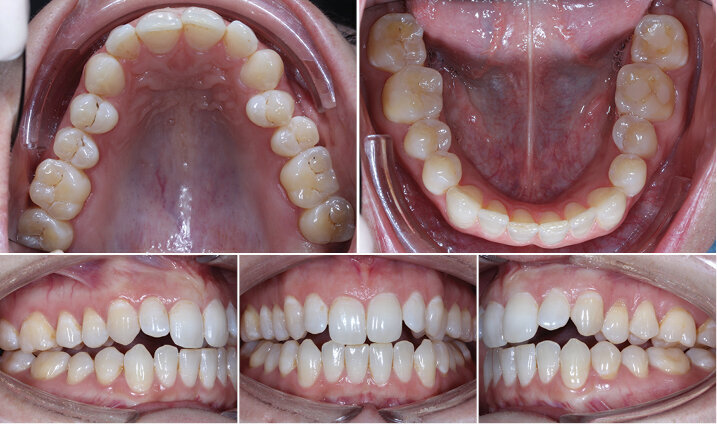

Vstupní intraorální fotografie

Konečná foto a RTG dokumentace